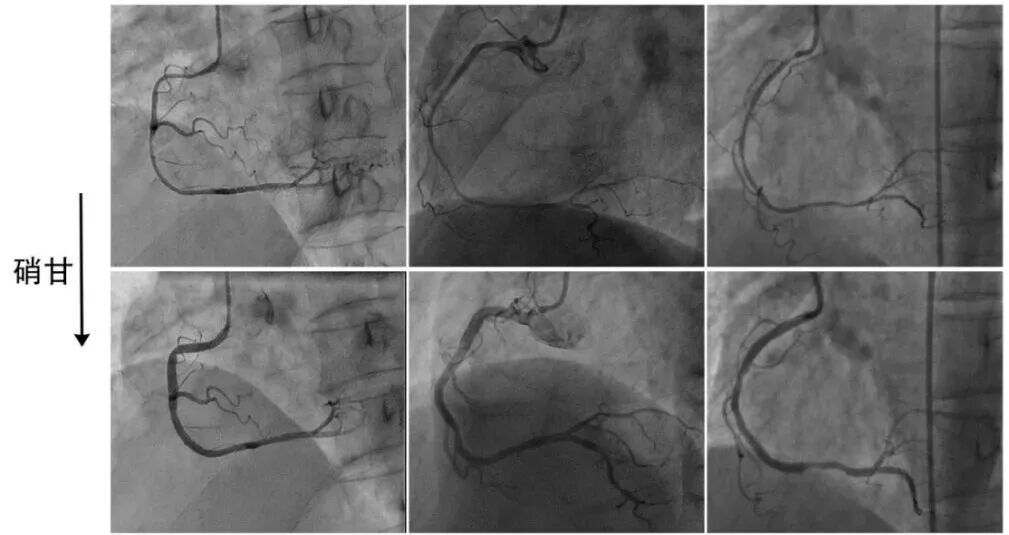

4、局部狭窄

首先强调,痉挛的本质是系统性的。但偶尔的,会遭遇局限性狭窄。一般见于二种情况,一是粥样硬化局部严重,在冠脉系统性张力升高基础上局部严重痉挛;二是局部机械刺激,譬如导管头或支架刺激。

痉挛性局部狭窄包括局限型、节段型、弥漫基础上节段型3种类型(图5-6)。局部狭窄很难想到痉挛,经常误诊。“见狭窄,上硝甘”需要成为习惯。

图5冠脉痉挛表现为局部狭窄,包括局限型、节段型、弥漫基础上节段型3种类型。

图6 多支局部痉挛[3]

51岁吸烟男性,凌晨急性胸痛30分钟,心电图II、III、avF、V5-6导联ST段抬高,急诊造影显示回旋支2处狭窄,右冠3处狭窄,冠脉内注射硝酸甘油后均缓解,心电图ST段回落,症状缓解。